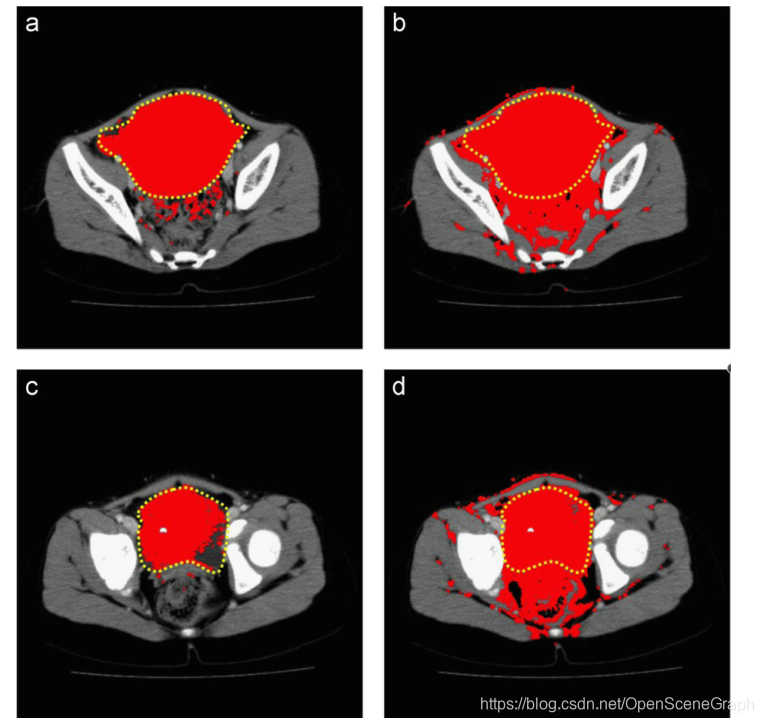

图5所示。黄色的是近似的肿瘤轮廓,红色的是实际的分割算法。灰度案例选择了很多不属于肿瘤的像素,导致FP值较高。(a) Dataset #1 colorization, slice #44, (b) Dataset #1 grayscale, slice #44, (c) Dataset #1 colorization, slice #49和(d) Dataset #1 grayscale, slice #49。(为了解释图的说明中对颜色的引用,请参考本文的web版本。)

对于FN值越高,着色方法效果越差的两个数据集,t检验没有显著性差异。只有三个数据集对灰度法产生了更好的FN结果,在统计上有显著差异,但这些数据集对相同的数据集也给出了更高的FP值。经过仔细研究,灰度算法选择了图像中很多不属于肿瘤的像素,导致FN值较低,FP值明显增加。一个例子是图5所示,w h e r e t h e算法图像灰度方法,增加像素的数量是肿瘤的一部分,产生较低的FN价值,但增加像素的数量,没有肿瘤的一部分,产生一个FP价值高。值得注意的是,尽管统计上FN值对灰度法更好,但它产生的FP误差比着色法高得多。对于边缘模糊、组织不均匀的B类肿瘤,灰度法根本不能分割出正确的像素点,如图6所示。然而,着色过程提高了分割结果,分割了大部分的实际肿瘤。对比两种方法的结果,灰度阈值选择的组织大多为健康组织存在较高的假阳性误差。这可能是由于健康组织与肿瘤组织有着非常相似的组织密度,因此转化为相似的灰度强度。钙化的异质性C类肿瘤与正常组织的肿瘤像元值不同,但灰度法无法利用不同的值,无法对肿瘤组织进行分割。即使两个组织之间存在不同的梯度,灰度像素值也不足以产生良好的分割结果。这些结果如图7所示。同样,着色能够改善结果,如图所示。对所有数据集进行了直方图分析,表明数据集具有多模态分布。此外,还对数据集的roi进行了直方图分析,结果是单模态和多模态分布的混合,特别是对于高钙化的肿瘤。结果显示,在着色过程后,特别是在对感兴趣区域的组织密度范围进行实时调整后,分割结果有了显著的改善。实时进行该过程后的重新着色过程,每100幅图像切片对分割结果的重新计算平均为1.9秒。着色过程强调了图像内的组织对比度,也限制了组织密度的范围,将被检查分割。如果在分割前着色对基本的分割方法有显著的改善,那么假设基于高级强度的分割方法也可以从着色中获得很大的好处。在保持高效和接近实时性能的同时提高分割精度的潜力将导致更快的病例诊断和改善患者护理。